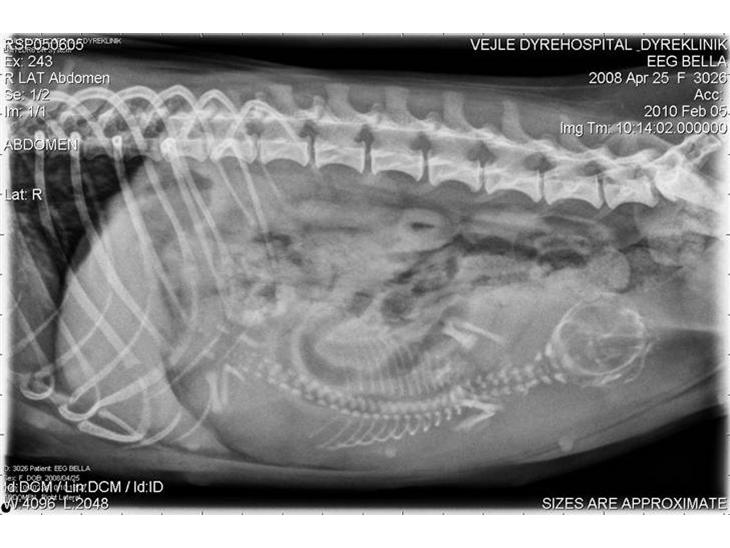

Bella´s røntgenbilleder, de første af baby Valentine.

Troede vi fik den bedste Valentines gave i år, men skæbne var ikke enig.

Så desværre måtte vi lade hende sove ind, 2 timer efter hun kom til verden.

Moder natur at en hård og bestemt dame, og Valentine`s havde ikke fået de bedste kort, så valgte hun skulle have fred.